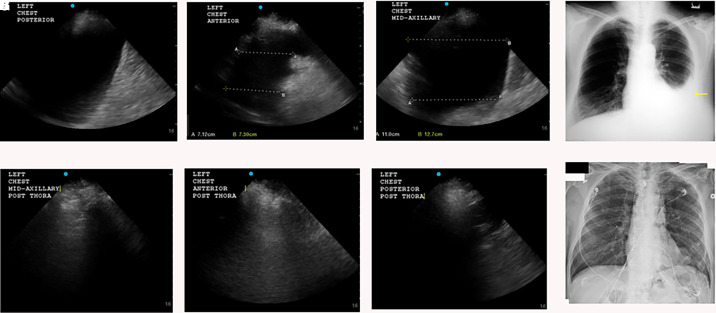

Rationale: Post-thoracentesis chest radiography (CXR) is often used to evaluate the degree of residual fluid after thoracentesis. Whether post-drainage ultrasound examination is comparable to CXR in the evaluation of pleural space evacuation is unknown. Objectives: How do post-thoracentesis ultrasound and CXR compare in assessing the effectiveness of pleural space evacuation? Methods: In this prospective, multicenter study, patients with free-flowing pleural effusions with minimal to no septations requiring thoracentesis were recruited. Post-thoracentesis ultrasound was performed immediately postprocedure; CXR was performed within 4 hours postprocedure. The primary outcome was agreement on complete pleural space evacuation between ultrasound and CXR. Complete pleural space evacuation was defined as the absence of pleural fluid on anterior, midaxillary, and posterior ultrasound views and lack of costophrenic angle blunting on CXR. Interobserver reliability was assessed via independent image reviews by two pulmonologists and two radiologists blinded to patient and procedure data, with disagreements resolved by a third reviewer. Results: Of the 147 patients enrolled (February 2021-May 2022), 145 were included in the final analysis. The median age was 64 years (56-75), and malignancy was the most frequent effusion etiology (n = 49). The lung was considered trapped in 50% (n = 73). A total of 826 ultrasound images were collected for blind review. The Gwet's agreement coefficient 1 assessing complete pleural evacuation between ultrasound and CXR was 0.93 (95% confidence interval [CI], 0.83-1.00). When assessing agreement on the basis of pre-specified criteria of effusion size (small vs. large), a substantial level of agreement was observed between ultrasound and CXR, indicated by a kappa of 0.64 (95% CI, 0.51-0.77). There was strong agreement (kappa = 0.81; 95% CI, 0.71-0.90) between proceduralist and blind ultrasound reviewers regarding complete pleural space evacuation. Conclusions: Post-thoracentesis ultrasound is an equally effective alternative to CXR in evaluating pleural space evacuation in simple pleural effusions.

简介:胸腔穿刺后胸部x线摄影(CXR)常用于评估胸腔穿刺后积液的程度。引流后超声检查是否可与CXR评估胸膜间隙排出性尚不清楚。研究问题:胸腔穿刺后超声与CXR在评估胸腔间隙抽吸效果方面的比较如何?方法:在这项前瞻性的多中心研究中,招募了有自由流动的胸腔积液且很少或没有分隔需要胸腔穿刺的患者。术后立即行胸腔镜超声检查;术后4小时内进行CXR。主要结果是超声和CXR在胸膜间隙完全清除方面的一致。完全胸膜间隙排空定义为在前、腋中、后超声上没有胸膜积液,在x光检查上没有肋膈角钝化。观察者间的可靠性由两名肺科医生和两名不了解患者/手术数据的放射科医生通过独立的图像评价进行评估,分歧由第三名评价者解决。结果:在纳入的147例患者中(2021年2月- 2022年5月),145例患者被纳入最终分析。中位年龄为64岁(56-75岁),恶性肿瘤是最常见的积液病因(n=49)。50%患者认为肺被困住(n=73)。共收集826张超声图像进行盲检。超声和CXR之间评估完全胸膜引流的Gwet一致系数1 (AC1)为0.93 (95% CI: 0.83-1.00)。当根据预先指定的积液大小标准(小与大)评估一致性时,超声和CXR之间观察到相当程度的一致性,kappa为0.64 (95% CI: 0.51-0.77)。在程序医师和盲超声审查员之间,关于完全胸膜间隙清除有很强的一致性(kappa= 0.81 (95% CI: 0.71-0.90))。结论:胸腔穿刺后超声在评价单纯性胸腔积液胸膜间隙排出方面与CXR同样有效。